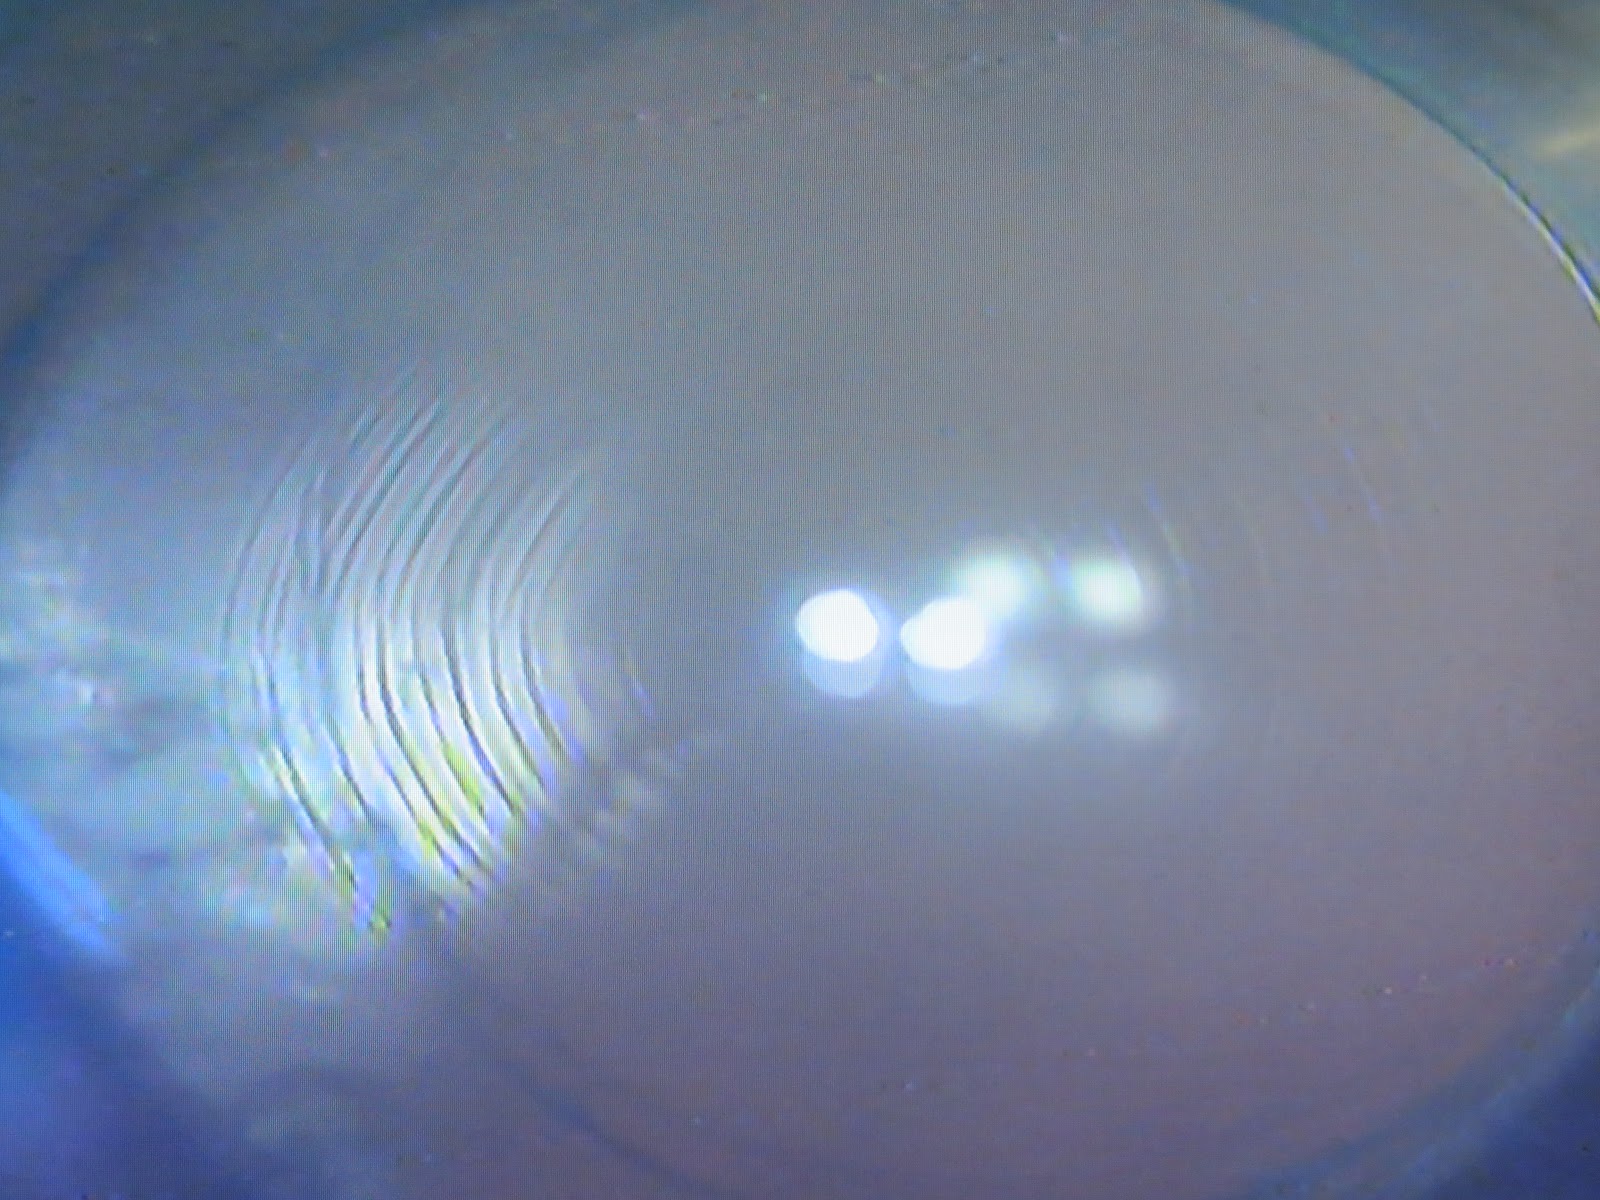

Zepto Precision Pulse Capsulotomy during Cataract Surgery Eyetube Zepto Laser Cataract Surgery   the zepto device simplifies this process by creating a capsulotomy in just three steps; Automating refractive cataract surgery with the zeptolink iol positioning system™. Precision centration on the visual axis.  zepto | the benefits at a glance: Precision is key to ensuring optimal outcomes. Instantaneous capsulotomy with potential to increase or efficiency.   zepto cataract surgery is the. Zepto Laser Cataract Surgery.